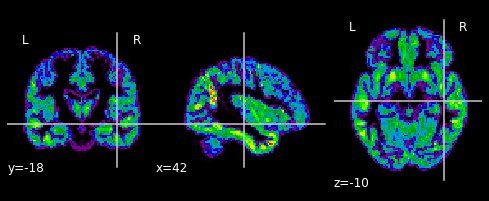

… and plot their gray matter densities.

for i in range(n_subjects):

plotting.plot_epi(gm_imgs[i])

plt.show()